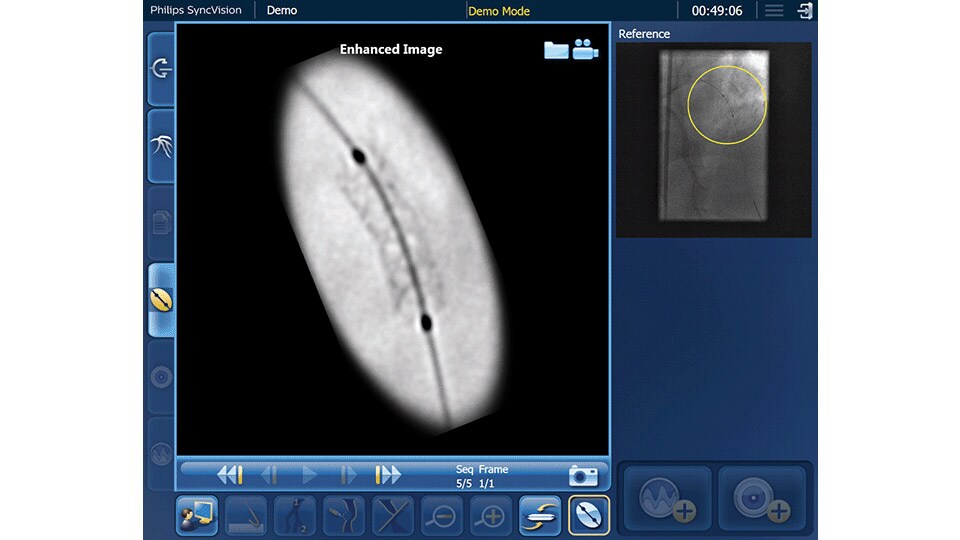

Device detection

Enhanced stent visualization quickly verifies positioning before and after deploying balloons and stents.